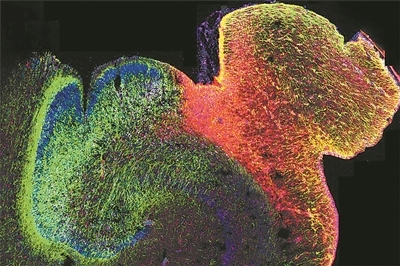

正在发育的人类海马体的荧光图像。

图片来源:美国加州大学旧金山分校

科技日报北京109日电 (记者张佳欣)由美国加州大学洛杉矶分校牵头的一项研究,揭示了人类大脑发育过程中基因调控的演变方式,并展示了染色质的3D结构在其中发挥的关键作用。研究人员绘制了海马体和前额叶皮质中DNA修饰的首张图谱,这两个大脑区域对学习、记忆和情绪调节至关重要,也常与自闭症和精神分裂症等疾病相关。这项研究为早期大脑发育如何影响身心健康提供了新的见解。相关研究9日发表在《自然》杂志上。